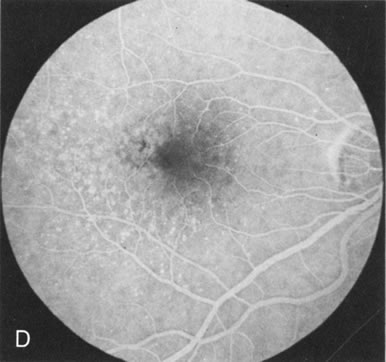

Of more clinical importance is the role of FA in the diagnosis and treatment of cystoid macular edema (CME) (Fig. 1C and D). Stereoscopic FA indicates that the leakage, which may be diffuse or have the typical petaloid stellate appearance of CME, can come from the perifoveal retinal capillaries, from the choroid through the RPE, or from a combination of both sources.4 With the recent suggestion that CME in RP may be successfully treated with acetazolamide,5, 6 FA is thus important to document the diagnosis of CME, establish the origin(s) of leakage, and follow patients during and after therapy.

In Oguchi's disease the hallmark fundus finding is a yellow metallic sheen (Fig. 2C). A similar sheen has been seen in progressive cone dystrophies and juvenile macular degeneration.7 In all these diseases the abnormal reflex does not affect the normal transmission of fluorescein dye (Fig. 2D). The normal FA suggests that, like findings in the carrier female in XLR RP, the abnormal retinal reflex in this disease is unrelated to pigment concentration or distribution.